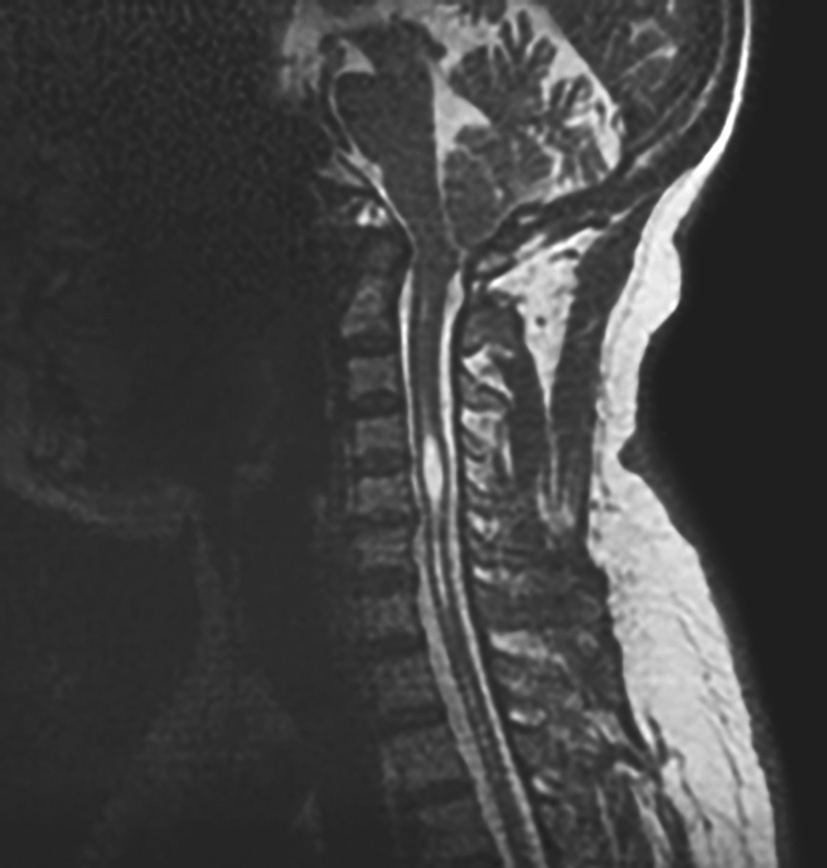

辅助检查:颈椎MRI提示Chiari畸形,合并颈髓空洞(图4-1-2)。

图4-1-2 颈椎MRI

(5)辅助检查:MRI可见小脑扁桃体下疝,合并颈髓空洞。

4.治疗过程 患者入院后,查颈椎MRI,提示Chiari畸形,脊髓空洞形成。查肩关节X线提示肩关节退变。完善相关术前检查及准备工作后,于全身麻醉下行“寰枕减压+硬膜成形术”。手术在电生理监测下进行,采用俯卧位。暴露枕骨鳞部和寰椎后弓后,将寰椎后弓切除约1cm宽骨槽,枕骨鳞部形成约4cm×4cm大小骨窗,松解寰枕筋膜后,因右侧硬膜上可见静脉窦,偏左侧大致Y字形剪开硬膜,使用人工硬膜行硬膜扩大成形。术后患者安返病房。

术后患者恢复良好,1周后拆线出院。出院前复查MRI可见通过减压+成形手术,解除了枕骨对小脑的压迫,扩大了寰枕区空间,使小脑扁桃体自然回缩,脑脊液循环恢复通畅。目前随访恢复良好。